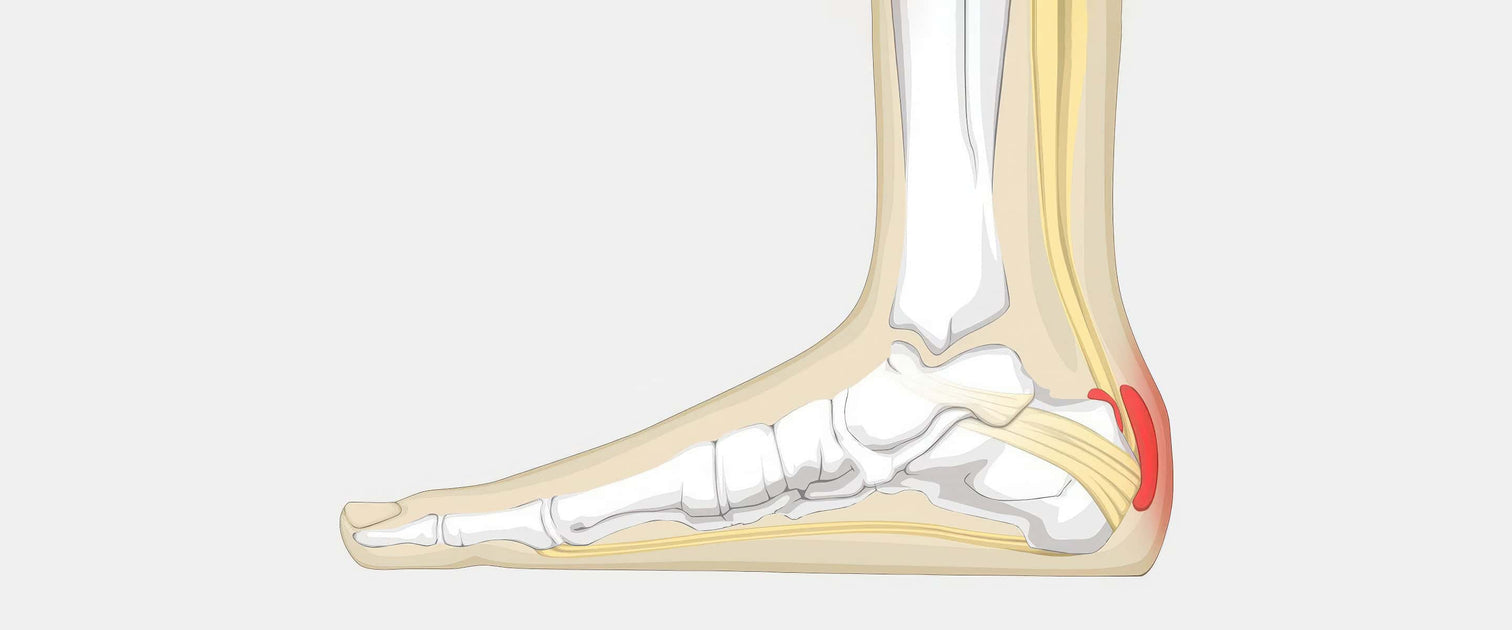

Running with heel bursitis should I do Achilles wedge stretches for Haglunds sale, Retrocalcaneal Bursitis Symptoms Causes Treatment sale, Insoles for Heel Bursitis ShoeInsoles sale, Orthotics for Bursitis SoleScience sale, Dr David Samra Sports Medicine Specialist Sydney sale, Retrocalcaneal Bursitis Symptoms Causes Treatment sale, Retrocalcaneal Bursitis Treatment OSMO Patch US sale, Retrocalcaneal Bursitis SLO Motion ShoesSLO Motion Shoes sale, Bursitis of the heel Information Mount Sinai New York sale, Heel Bursitis Cause Symptoms Treatment Exercise sale, Amazon Heel Bursitis sale, Heel Bursitis Treatment Arthritis health sale, Heel Bursitis Treatment Long Island Foot Doctors Massapequa Podiatry Associates P.C sale, Medial Lateral Heel Wedge Silicone Insoles Supination Pronation Corrective Heel Insoles Gel Adhesive Shoe Inserts for Foot Alignment Knock Knee sale, Bursitis of the heel Information Mount Sinai New York sale, Achilles Bursitis The Complete Injury Guide Vive Health sale, San Luis Podiatry Group sale, Heel Bursitis Causes and Treatment YouTube sale, Bursitis A Real Pain in the Heel sale, What Is Retrocalcaneal Bursitis Symptoms Causes Prevention Treatment sale, Heel Bursitis The Foot and Ankle Clinic sale, Retrocalcaneal bursitis Physioline sale, 12 Best Execise for Retrocalcaneal Bursitis Samarpan Physiotherapy Clinic sale, Heel Bursitis The Foot and Ankle Clinic sale, Retrocalcaneal Bursitis Achilles Tendon Swelling Heel Pain sale, Retrocalcaneal bursitis Physioline sale, Retrocalcanel Bursitis 4 Life Podiatry sale, 416 Running with heel bursitis should I do Achilles wedge stretches for Haglunds DOC sale, Achilles Bursitis Heel Pain PhysioAdvisor sale, Achilles tendon support with septate friction pads and insulated heel wedge. Septate pads gently massage the oedema away from the paratenon during sale, Achilles Bursitis Causes Symptoms Treatment sale, Can Achilles Bursitis Be Treated Without Surgery Island Foot Clinics sale, Medi AchiMed SAND Achilles Tendon Support with Gel Heel Cup Brace Bursitis Sports I 18 20cm Amazon Health Personal Care sale, Retrocalcaneal bursitis The ankle Biomechanical problems What We Treat Chiropody Leading chiropodist Podiatrists in Manchester and Liverpool sale, Achilles Bursitis Rehab 49 sale.

Heel wedges for bursitis sale